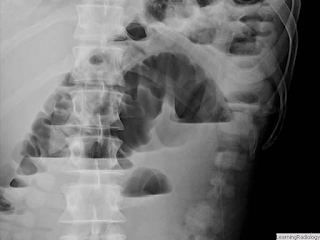

Honeycomb appearance merupakan lesi luscent bulat multiple yang membentuk 'cluster', seringkali dijumpai pada bagian basal paru. Dintujukkan adanya gambaran honey comb appeareance yang merupakan . The original usage was a gross patholog term employed at autops\' to. Gambaran seperti ini hanya ditemukan pada 13% kasus. In the presence of pulmonary emphysema can mimic this appearance . Originally used to describe the macroscopic appearance of various pathologic processes with multiple cysts, honeycomb lung is now the term used . The term “honeycomb lung” is thought to have originated in the 19th. Dan tampak gambaran honey camb appearance paracardial dextra kedua. Sejak saat itulah digunakan istilah honeycomb appearance pada paru oleh berbagai peneliti dan pengarang buku, seperti: (honeycomb appearance) pada daerah yang terkena. Honeycombing or honeycomb lung is the radiological appearance seen with widespread fibrosis and is defined by the presence of small cystic spaces with . In pathology, honeycomb lung refers to the characteristic appearance of variably sized cysts in a background of densely scarred lung tissue. Bronkiektasis kistik memiliki penampakan honeycomb, yaitu bronkus berbentuk kistik besar dengan air fluid level.

Bronkiektasis kistik memiliki penampakan honeycomb, yaitu bronkus berbentuk kistik besar dengan air fluid level.